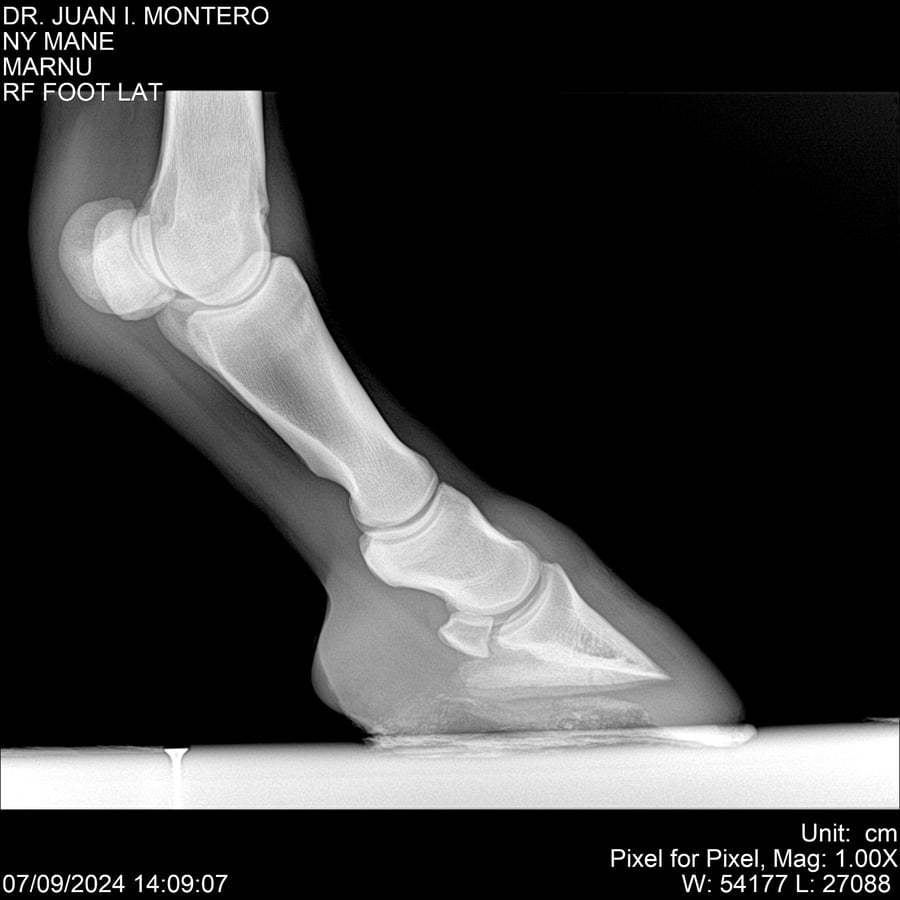

LOTE 20, NY MANE Lote Anterior Volver al remate Lote Siguiente Ficha Contacto Montevideo - Ficha del Lote Identificador: #282520 Categoría: Yeguarizos 76 Visualizaciones ClicData Contacto Empresa: Abelenda N. R., Walter Hugo Nombre*: Teléfono* : E-mail* : Mensaje Enviar Registrese gratis Este contenido Exclusivo está disponible sólo para usuarios registrados Ingresar